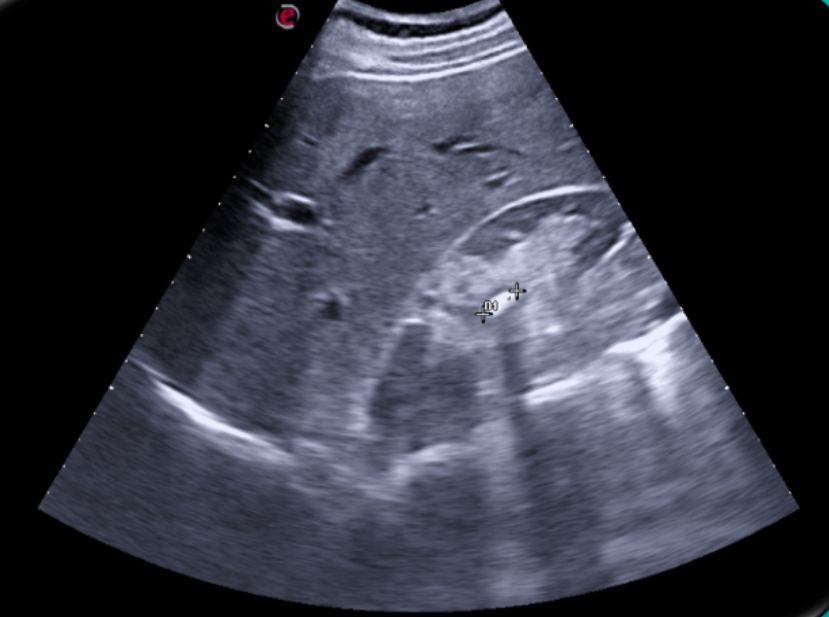

Expondremos la utilidad de la EC como herramienta en el manejo de los pacientes con diferentes tipos de dolor que atiende el Médico de Familia en las consultas diarias, urgentes, e incluso en los domicilios, en diversos escenarios clínicos a los que podemos enfrentarnos en nuestra práctica clínica habitual, desde un dolor visceral (abdominal, torácico, urológico o ginecológico), un dolor músculo-esquelético (traumático o no, con sospecha de fractura u osteoartrósico incapacitante), un dolor vascular (sospecha de trombosis venosa profunda, trombosis arterial aguda, aneurismático); ayudando a obtener una información crucial con un método no invasivo que nos ayudará a reducir la incertidumbre y orientar mejor el diagnóstico de nuestros pacientes e incluso nos podrá ser muy útil como herramienta con fines terapéuticos como en el caso de las infiltraciones ecoguiadas.

En nuestra experiencia como Centro de Salud que utiliza de forma rutinaria la Ecografía clínica, hemos visto un importante avance en nuestra capacidad resolutiva en muchos casos, mejorando el diagnóstico diferencial de los diferentes tipos de dolor, su abordaje terapéutico precoz, e incluso ayudando a los pacientes a una mejor comprensión de su patología.

Consideramos la Ecografía clínica como una herramienta de gran utilidad en la consulta de Atención Primaria, que puede aportar gran ayuda al Médico de Familia en la toma de decisiones, ayudando a obtener diagnósticos diferenciales precoces y que también ayuda a agilizar las derivaciones pertinentes al conseguir en muchos casos un enfoque diagnóstico más preciso.